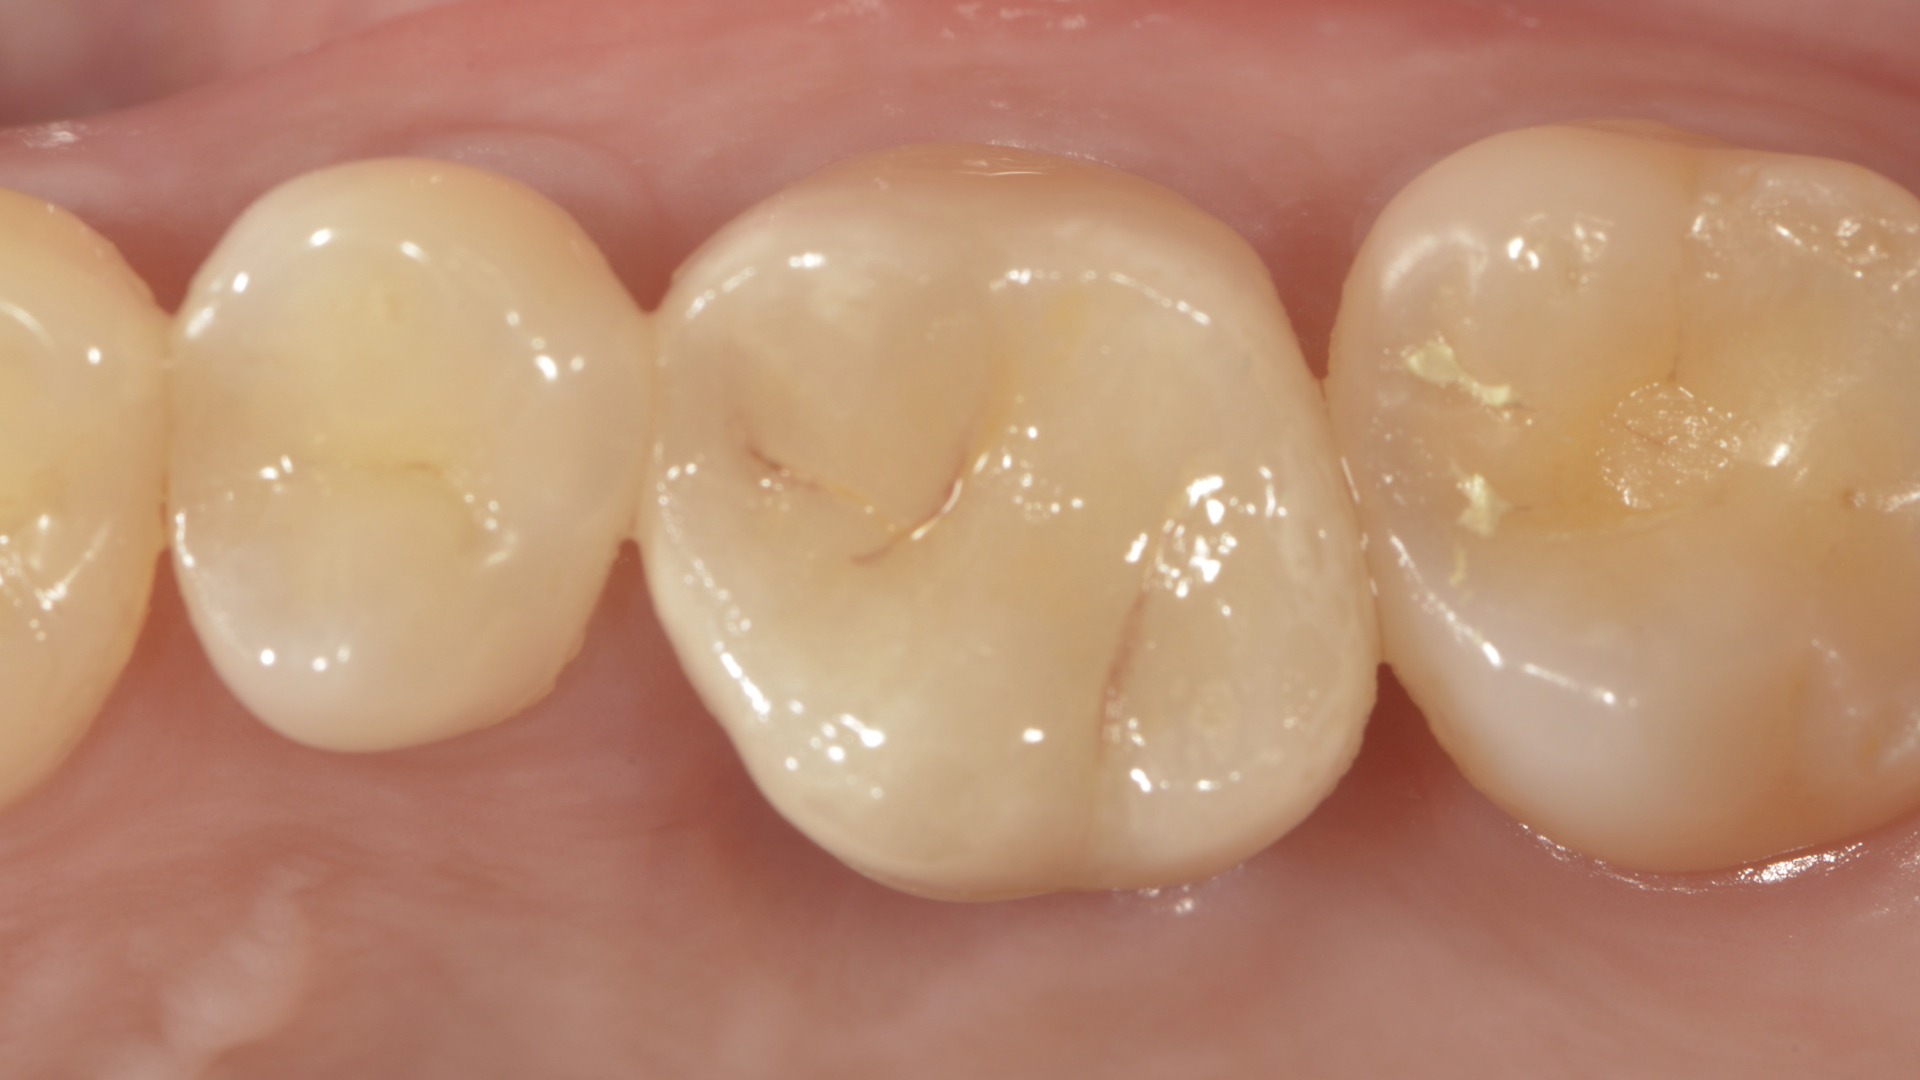

全瓷嵌體完成